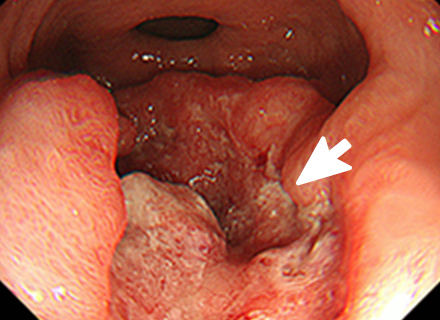

早期胃がんの内視鏡的治療

内視鏡治療の対象となる胃がんは、病変が一括で取れる部位と大きさであり、リンパ節転移の可能性がほとんどないほぼ粘膜内にとどまっていると診断された早期胃がんになります。

内視鏡的治療が外科手術に比べ優れた点は、入院期間が短い上に、おなかに傷がつかず、大きな併発症がなければ退院後の食生活、社会生活に支障がないことです。劣っている点は、切除した組織の状態によっては遺残病変の有無が確認困難な場合があり、将来再発する可能性があることや、切り取った病変の組織検査の結果、局所にがん細胞が残っている可能性がある場合や、がんがリンパ節に転移している可能性があると判断された場合は、さらに外科手術が必要になることです。

内視鏡を使った早期胃がんの治療法には、内視鏡的粘膜切除術(EMR)と内視鏡的粘膜下層剥離術(ESD)の2種類があります。

内視鏡的粘膜下層剥離術:ESD(Endoscopic submucosal dissection)

専用の処置具を使いより広範囲に病変を切り取ることが可能な治療法です。切り取られた病変は、最終的に顕微鏡でその組織の様子が確認されます(病理検査)。この方法では、大きな病変をひとかたまりで取り、病理検査でより正確な診断を行うことができます。

ESDは大きな病変も一括して切除可能ですが、手技が煩雑で時間がかかり、出血や穿孔などの併発症が生じる場合があります。ほとんどの場合内視鏡的に止血可能ですが、稀には輸血、開腹手術などを要することがあります。

大腸ポリープまたは早期大腸がんの内視鏡治療

良性のポリープや早期がんの中でも粘膜だけにとどまっているもの、粘膜下層へわずかに広がっているものが内視鏡治療の適応となります。 小さなポリープに対しては、鉗子でつかみながら高周波電流を用いて病変の根もとを焼き切ります(ホットバイオプシー)。 茎のあるポリープに対しては、輪の形のスネアを茎の部分でしめ、高周波電流を用いて切断します(ポリペクトミー)。 茎のない病変に対しては、内視鏡的粘膜切除術(EMR)や内視鏡的粘膜下層剥離術(ESD)などを行います。